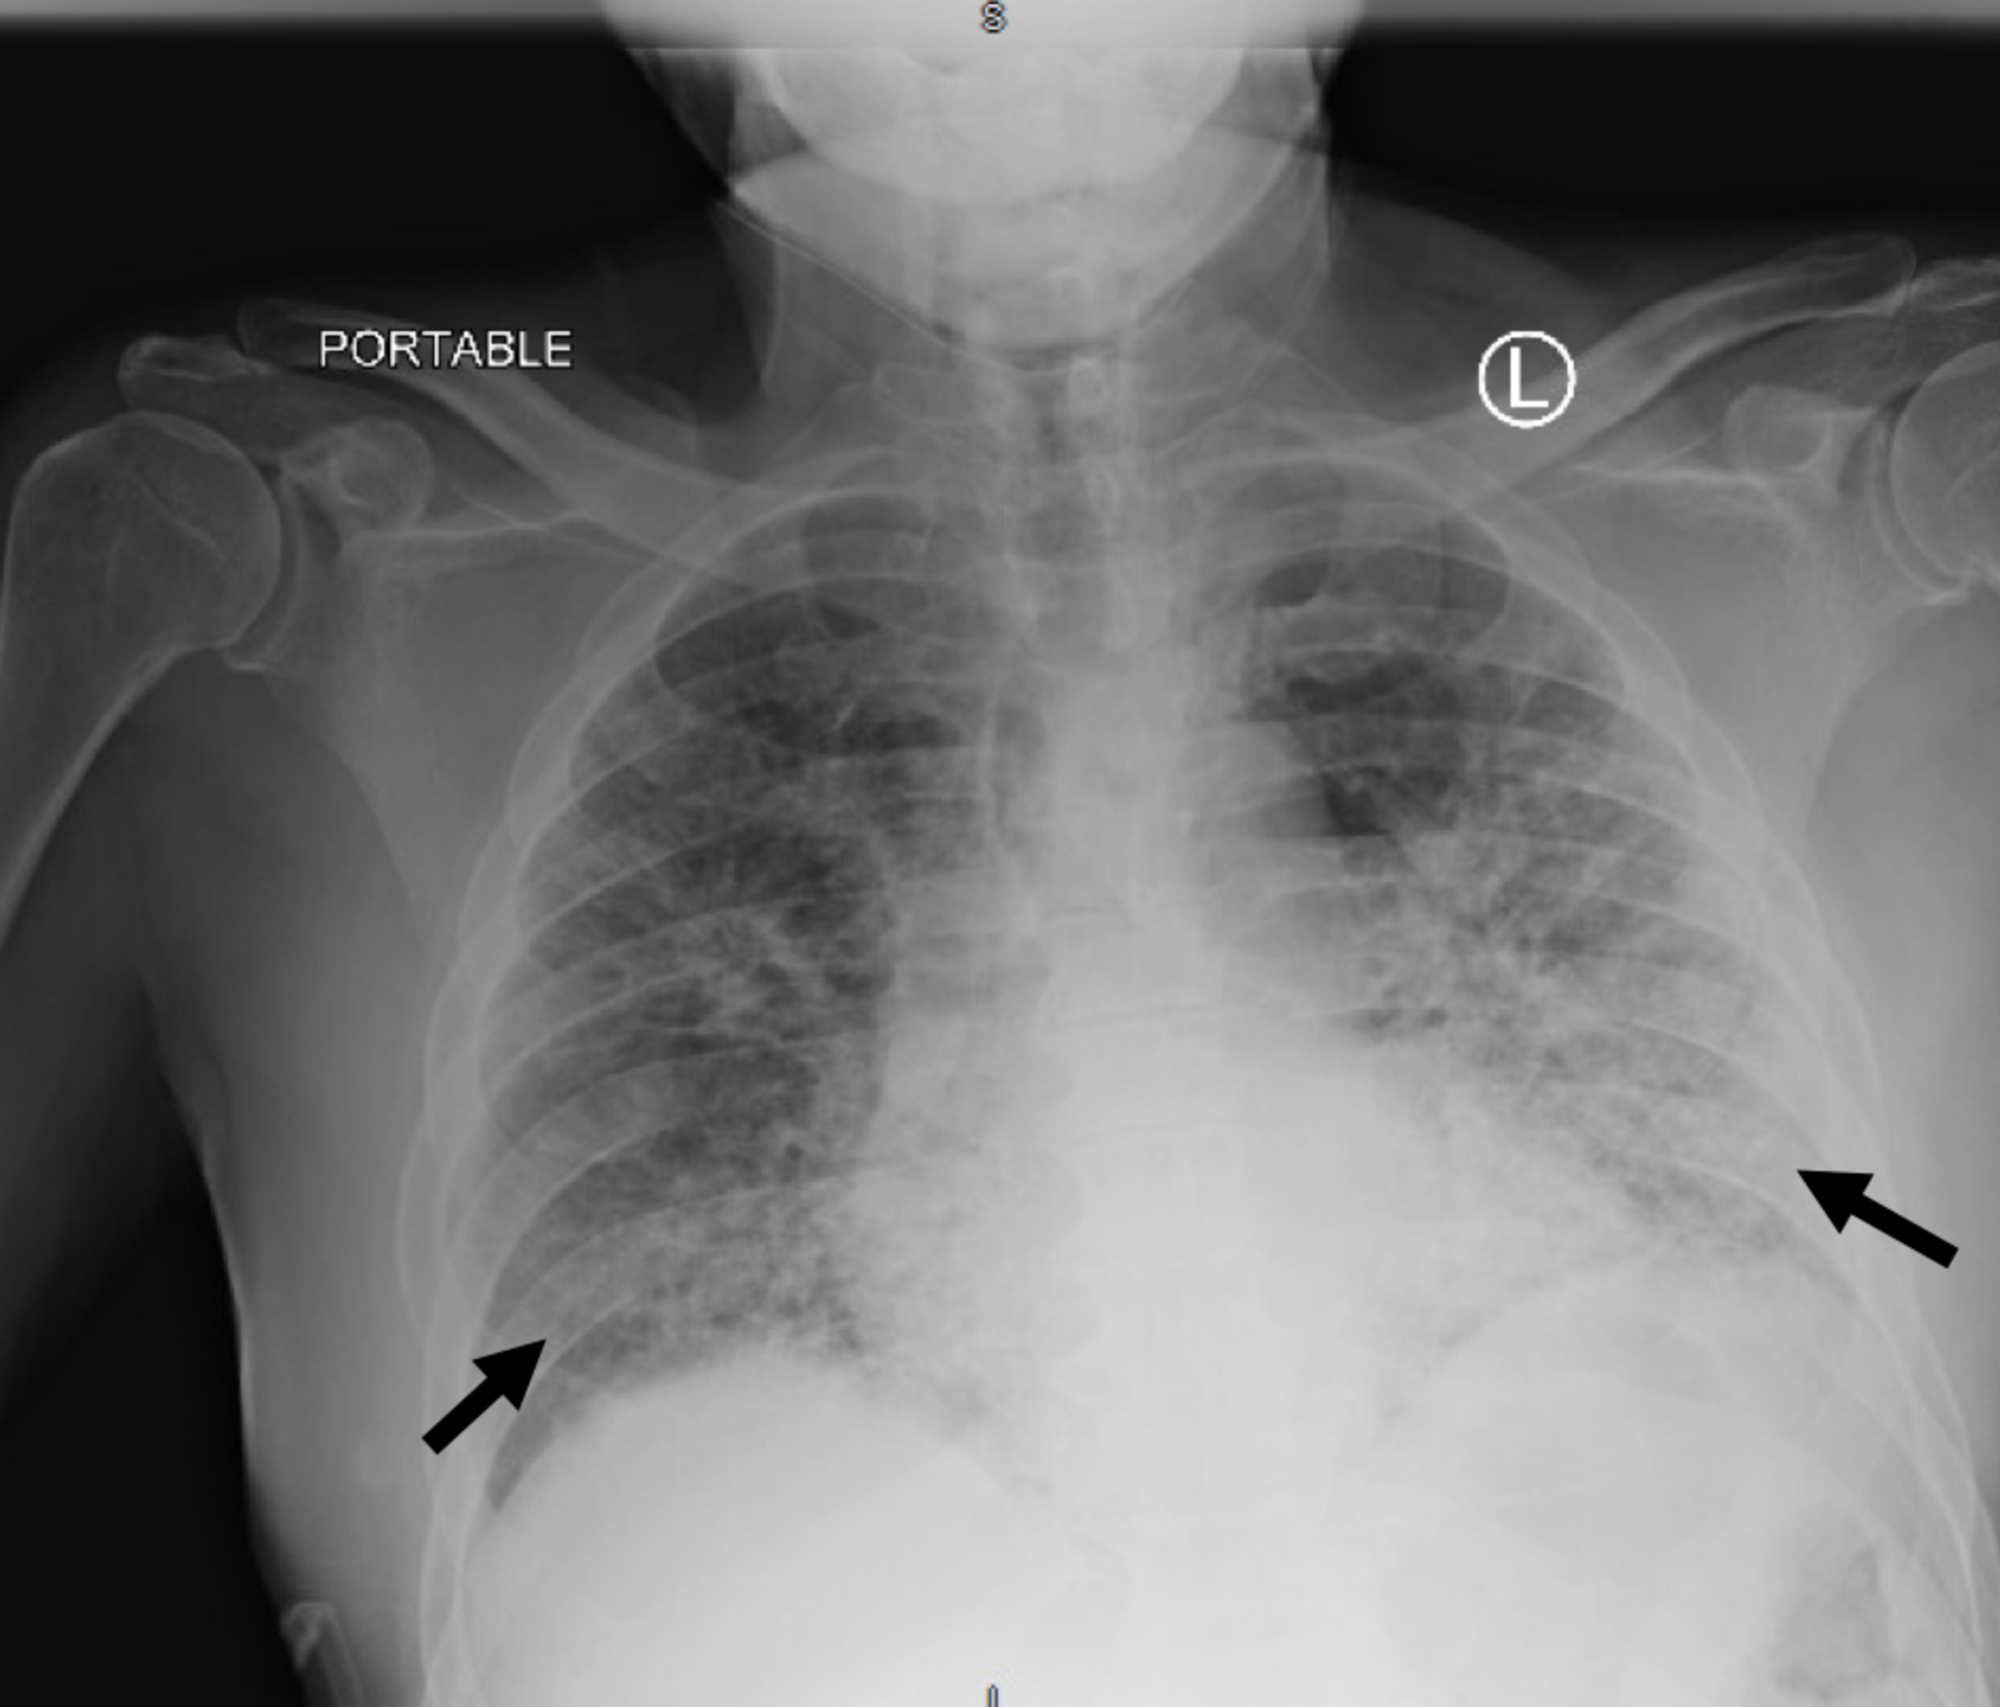

Ground Glass Opacity In Lungs On Chest X Ray X Ray Ground Glass Appearance Ground glass looks hazy or cloudy compared to the normal dark lung. These areas show increased density inside the lungs which could indicate. In fact, ggo is a. Ground glass opacity (ggo) refers to the hazy gray areas that can show up in ct scans of the lungs. The finding can be one small spot all the way to involve. X Ray Ground Glass Appearance.

From mavink.com

Ground Glass Opacities Chest X Ray X Ray Ground Glass Appearance Ground glass opacity (ggo) refers to the hazy gray areas that can show up in ct scans of the lungs. Ground glass looks hazy or cloudy compared to the normal dark lung. In fact, ggo is a. The finding can be one small spot all the way to involve the lungs throughout. These areas show increased density inside the lungs. X Ray Ground Glass Appearance.

From www.slideshare.net

Chest X Ray Interpretation X Ray Ground Glass Appearance Ground glass opacity (ggo) refers to the hazy gray areas that can show up in ct scans of the lungs. In fact, ggo is a. The finding can be one small spot all the way to involve the lungs throughout. Ground glass looks hazy or cloudy compared to the normal dark lung. These areas show increased density inside the lungs. X Ray Ground Glass Appearance.